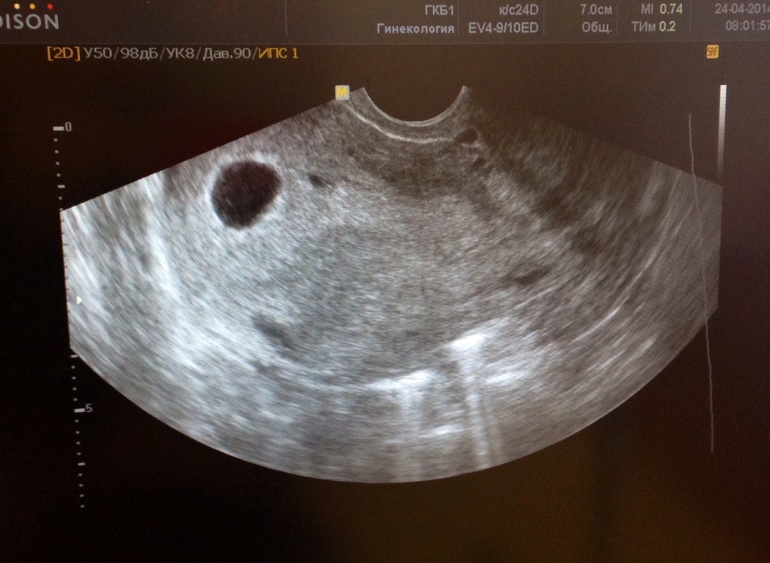

Начальный уровень ХГЧ (611 мЕд/мл) соответствует 14-21 дню после зачатия. Срок от зачатия 2-3 недели, акушерский срок 4-5 недель.У вас нормальный уровень ХГЧ.Конечный уровень ХГЧ: 1373 мЕд/мл. За 2 дня уровень увеличивается на 124.713584288% — динамика быстрая, возможна многоплодная беременность. Норма 60-100%.